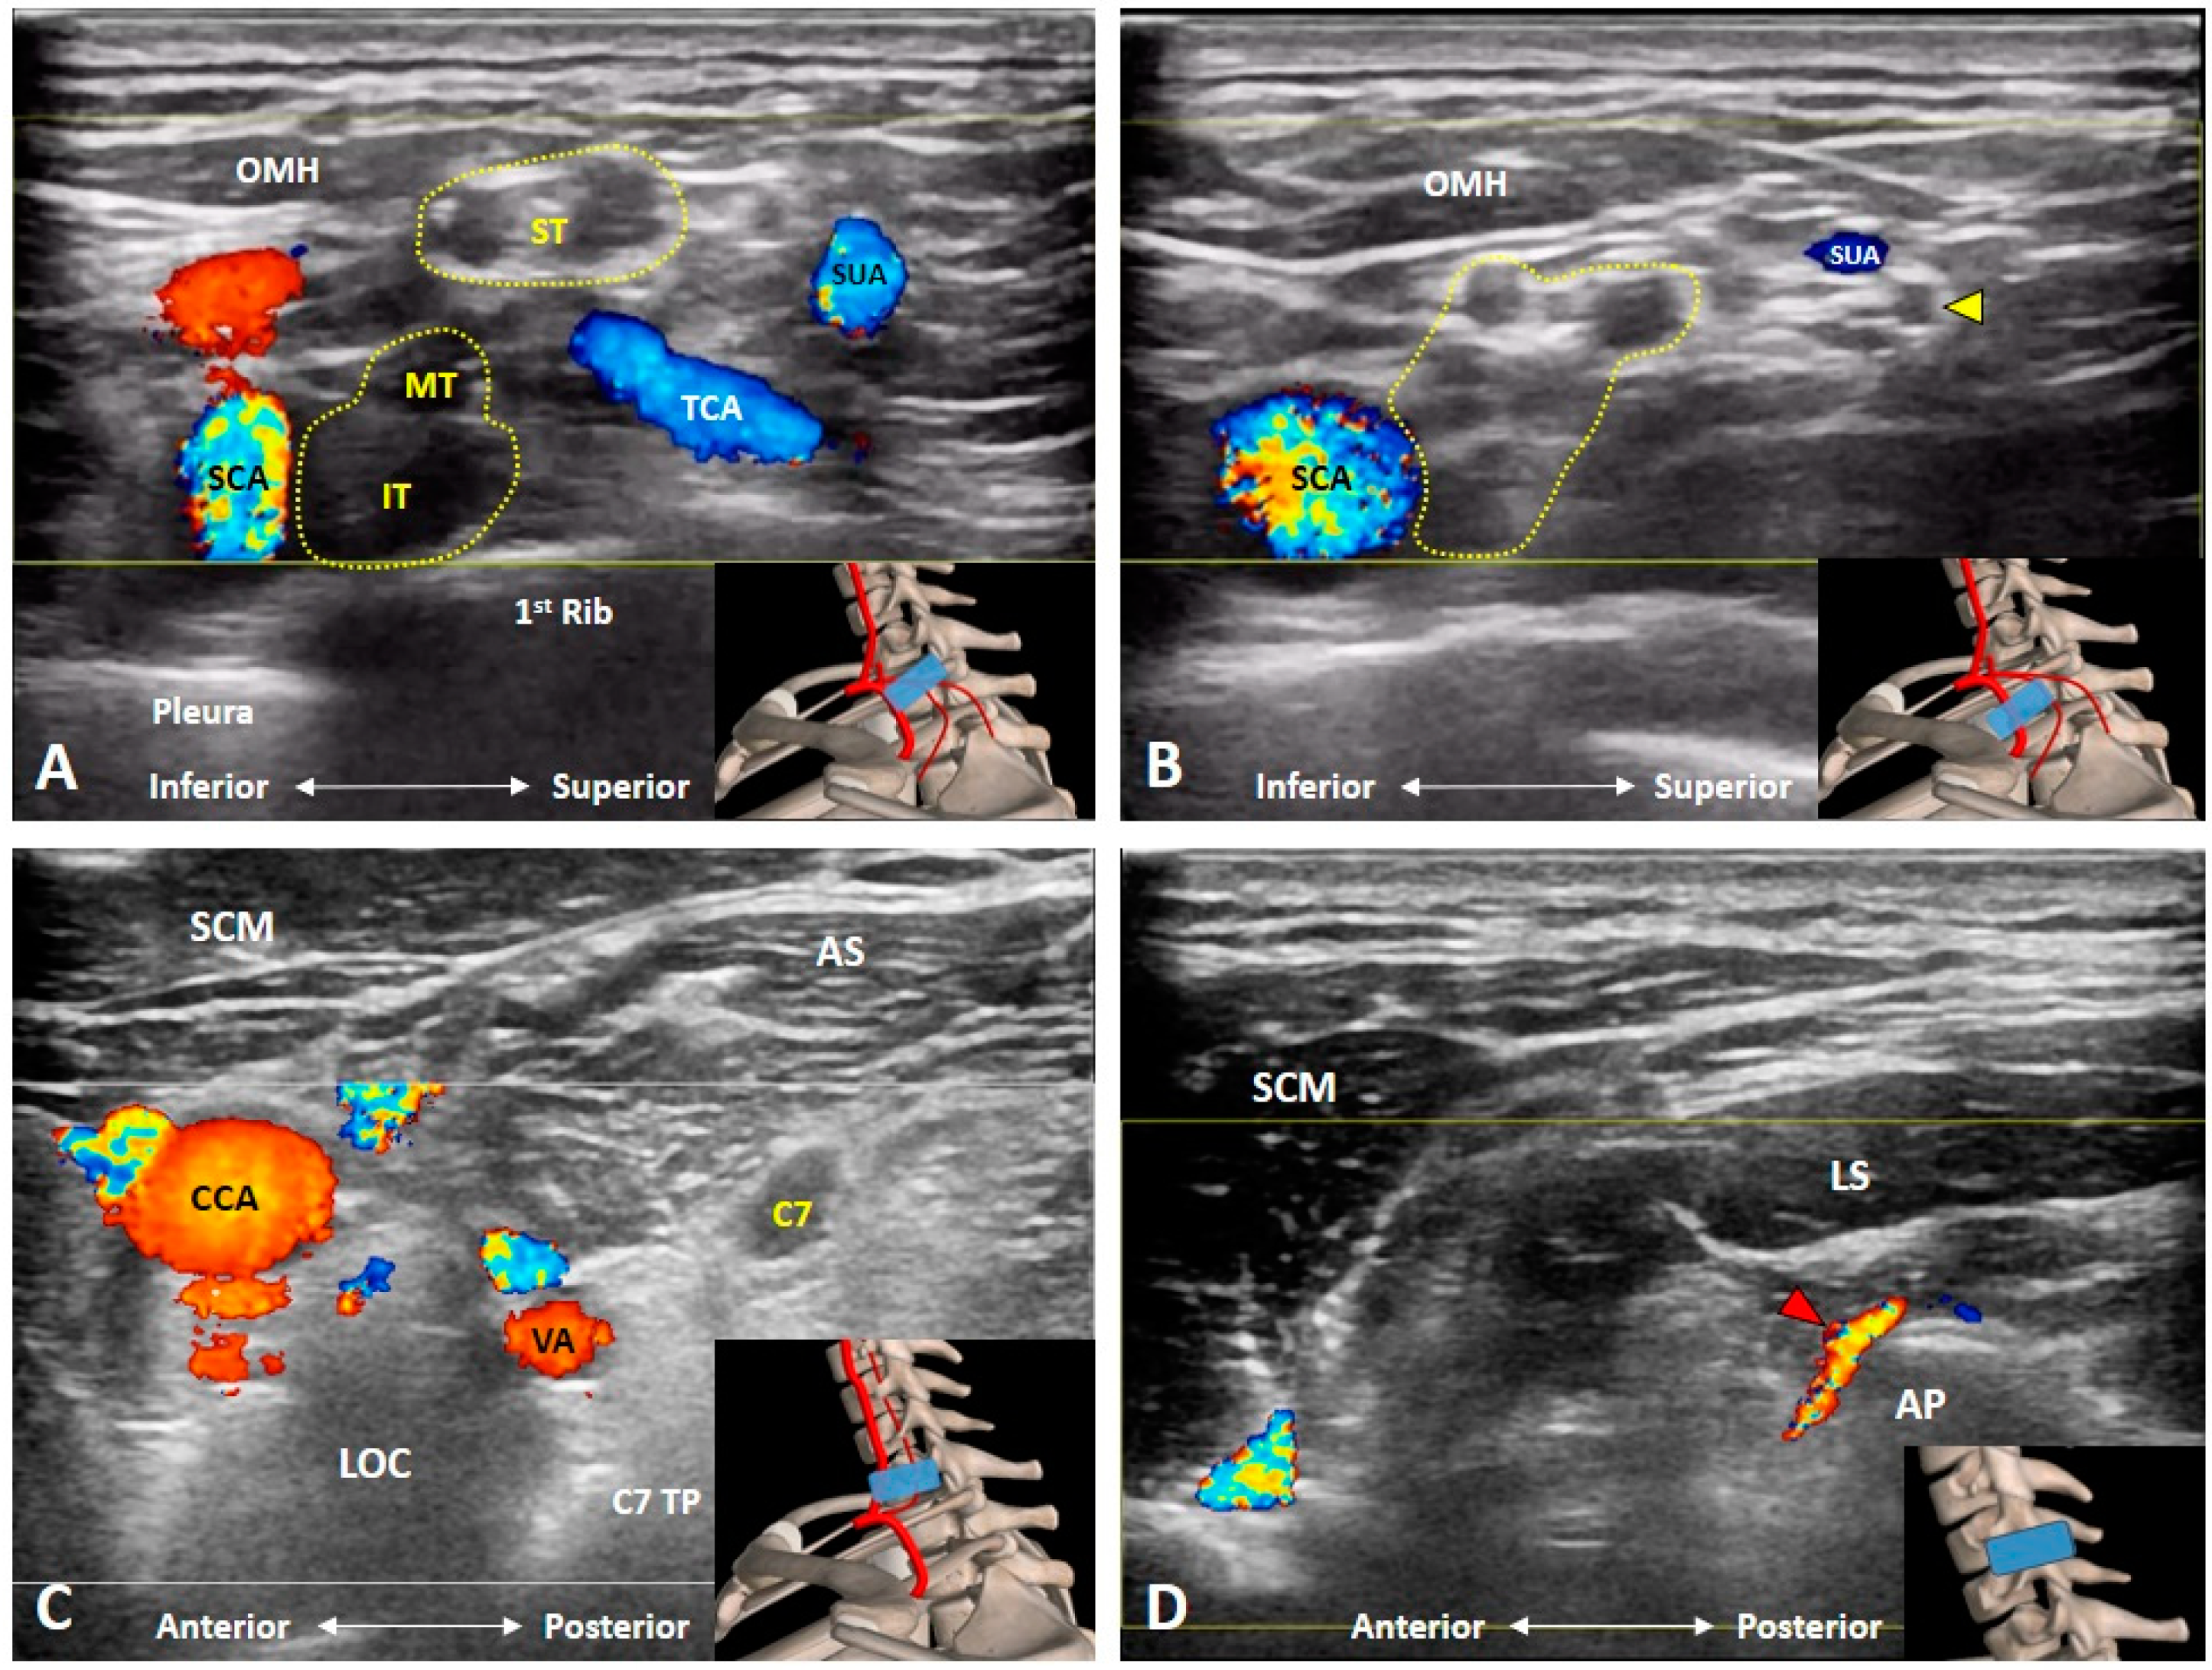

3.5. Which Vascular Structure(s) Should We Be Aware Of?

3.6. Which Branches of the BP Can Be Seen in the Cervical Region?